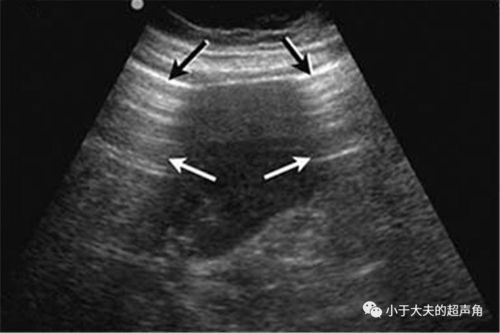

节育环嵌顿b超声像图

节育环嵌顿b超声像图,节育环嵌顿超声图片

节育环嵌顿超声图片

节育环b超图片

节育环b超图片欣赏

b超带环图片

上环b超单检查图片

正常环位置b超图片

b超查环图片